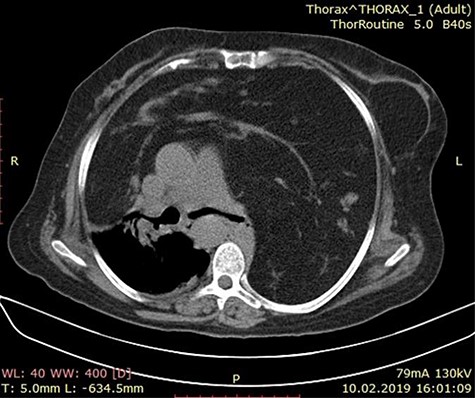

A 60-year-old female patient presented to the emergency with complains of dyspnea, non-productive cough and chest pain for 2 months. There is no history of hemoptysis, weight loss and substance abuse. On physical examination, oxygen saturation was 64%, blood pressure was 170/110 mm Hg, temperature was 97.9°F (36.6°C) and blood sugar was normal. Local examination of the chest revealed limitation in chest movement and decreased tactile focal fremitus on both sides of the chest. On percussion, dullness on both sides of the chest was noticed. On auscultation, decreased breath sounds on both sides of the chest were detected and the apex beat of the heart was displaced on the right side. The blood tests performed in the emergency room were in normal range. She underwent radiological evaluation with chest X-ray that revealed diffuse infiltration on both lungs (Fig. 1). Thoracic echocardiography revealed huge mediastinal mass with dextrocardia. This was followed by chest computed tomography (CT) that showed bilateral diffuse mediastinal mass, which involves fatty tissue containing soft tissue streaks that probably represent islands of normal thymic components with no infiltrations (Figs. 2–3). We concluded that the only curative treatment of thymolipoma is surgical excision. Unfortunately, despite the patient being told about the surgical procedure, she did not give the permission and passed away a week later due to secondary compression to the lungs.

Axial chest CT image showing a mass lesion with wide range of fat density filling both hemithorax was observed, including linear and nodular densities in the right hemithorax. A dense retrosternal mass displacing both lungs and chest. No evidence of invasion is seen.